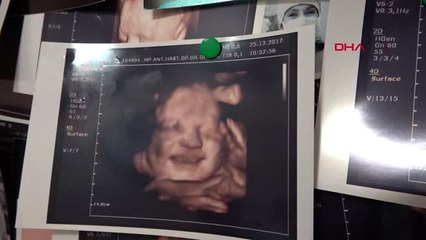

Prof. Dr. Cansun Demir Omega 3 takviyesi alan bebeklerin IQ'su çok daha yüksekTÜRK Jinekoloji ve Obstetrik Derneği (TJOD) 2'nci Başkanı Prof. Dr. Cansun Demir, hamilelikte Omega-3 takviyesi alan kadınların çocuklarının IQ'sunun ilerleyen yıllarda, diğerlerine göre daha yüksek olduğunu belirtti. brProf. Dr. Cansun Demir Omega 3 takviyesi alan bebeklerin IQ'su çok daha yüksekbrbrTÜRK Jinekoloji ve Obstetrik Derneği (TJOD) 2'nci Başkanı Prof. Dr. Cansun Demir, hamilelikte Omega-3 takviyesi alan kadınların çocuklarının IQ'sunun ilerleyen yıllarda, diğerlerine göre daha yüksek olduğunu belirtti.brbr15'inci Türk Jinekoloji Obstetrik Kongresi ve 25'inci Avrupa Jinekoloji ve Obstetrik Derneği'nin Kongresi ortak şekilde Antalya'da düzenlendi. Kongrenin basın toplantısına TJOD Başkanı Prof. Dr. Ateş Karateke, TJOD 2'nci Başkanı Prof. Dr. Cansun Demir ve Avrupa Jinekoloji ve Obstetrik Derneği (EBCOG) Başkanı Dr. Tahir Mahmood katıldı. Toplantıda Prof. Dr.